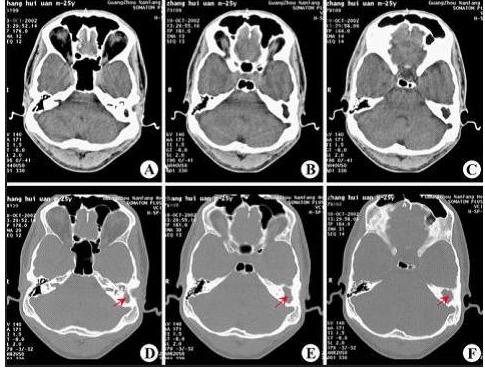

CT显示:左侧慢性中耳乳突炎(胆脂瘤型)

乳突炎常继发于中耳炎,引起乳突粘膜充血及水肿,分泌物增多。继续发展可破坏气房间隔,甚至破坏乳突骨壁而向颅内、外穿破。乳突炎转为慢性后,乳突内充满肉芽和脓液,破坏骨质,刺激新骨增生,当鼓膜穿破后,外耳道上皮长入中耳及鼓窦,部分上皮坏死及变性后,形成胆脂瘤。